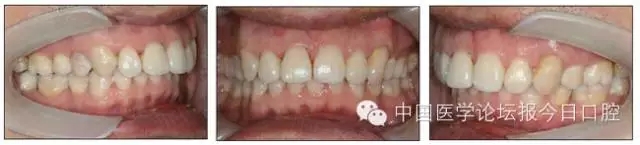

口內情況:恒牙列,24、34、44缺失,磨牙Ⅲ類關系,上牙列散隙,上前牙扇形漂移。前牙深覆(牙合)、深覆蓋。口腔衛(wèi)生較差,11與12間牙齦乳頭紅腫,多個牙探診有牙周袋形成,11松動Ⅰ度,余切牙松動(-),患者面像及口內像如圖1、2所示。

圖2 治療前口內像

圖9 治療后口內像